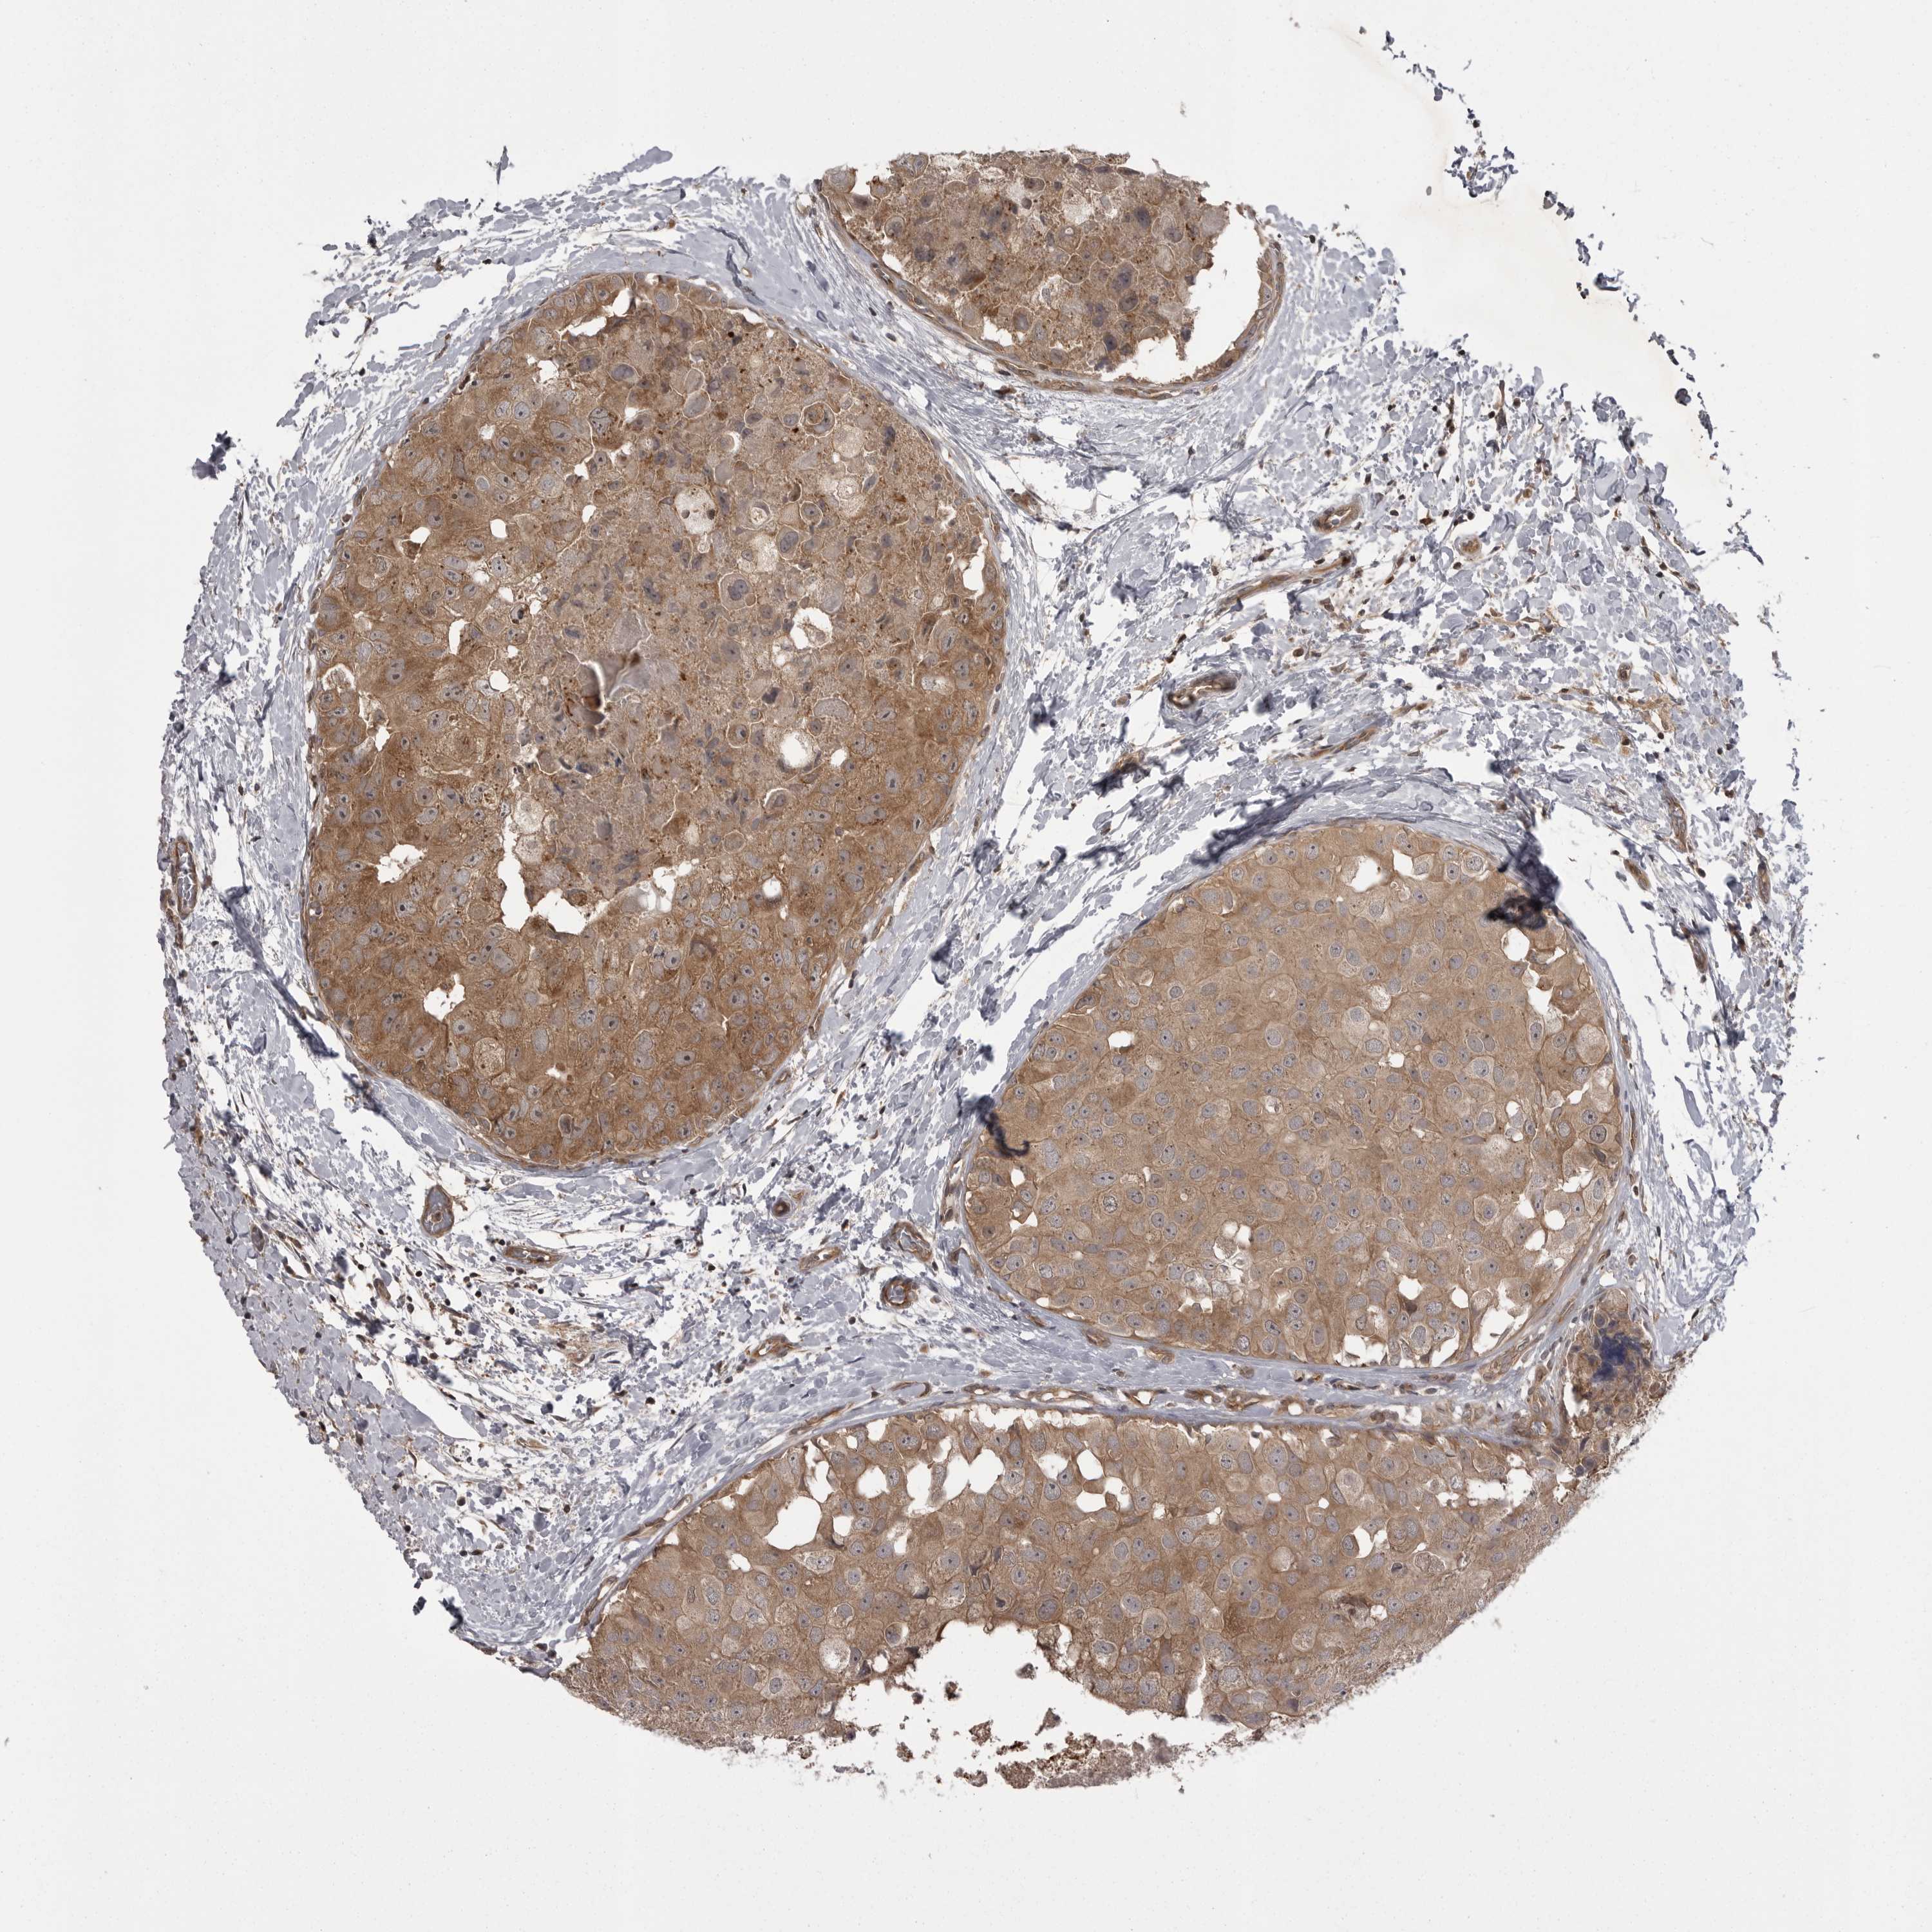

CANCER BREAST CANCER Show tissue menu

BRCA TCGA BRCA VALIDATION PROTEIN EXPRESSION